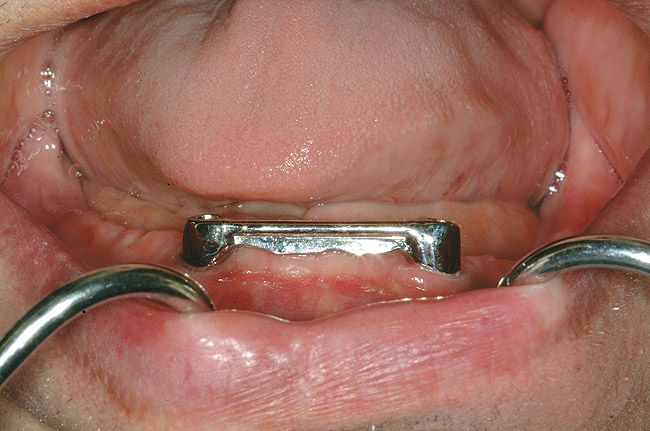

Figure 4  An example of a two-implant tissue bar for an implant-assisted prosthesis.

Figure 4

When dental implants were introduced by Brånemark, they were intended primarily for the completely edentulous patient, specifically the edentulous mandible. The initial prosthesis was a fixed restoration commonly referred to as a fixed bone anchored bridge. That particular prosthetic design is now the fixed-detachable hybrid prosthesis and has been highly successful for both the implants and prostheses.12,13 Implants have also been used for overdenture restorations14 and can be implant-assisted or implant-supported. With implant-assisted prostheses, the implants and mucoperiosteum share the forces of occlusion. A simple two-implant overdenture, either a Hader Bar® (Sterngold™, www.sterngold.com) or Locator® abutment (Zest Anchors, www.zestanchors.com), are examples of implant-assisted overlay prostheses and are always a removable restoration (Figure 4 and Figure 5). With implant-supported prostheses, the forces of occlusion are borne solely by the implants. This prosthesis can be an overlay prosthesis or a fixed restoration. Milled bar restorations, overdentures with bar substructures, and metal–ceramic restorations attached to implant abutments by either screws or cement are examples of implant-supported restorations. One of the primary benefits of using dental implants in edentulous patients is the preservation of the residual bone, which will provide a better opportunity for future successful prosthetic restorations.